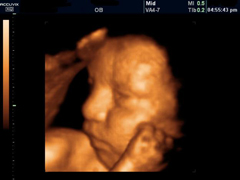

Трансвагинальное УЗИ является более точным методом. В последнее время весьма распространенными способами получения дополнительной информации о беременности считаются трехмерное и четырехмерное УЗИ плода.

Четырехмерное или 4D-УЗИ плода позволяет увидеть объемное изображение ребенка в реальном времени, при этом видны его движения и работа всех внутренних органов.